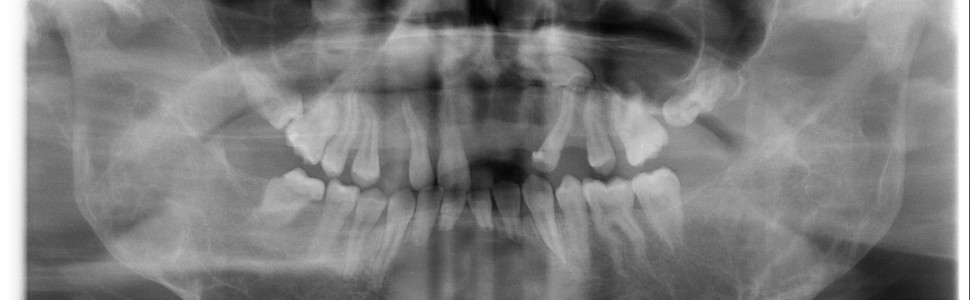

Wieloletnie obserwacje zmian w cherubizmie na podstawie zdjęć rentgenowskich. Opis przypadku i przegląd piśmiennictwa

Cherubizm jest rzadkim, występującym rodzinnie włóknistym zwyrodnieniem kości szczęk. Śródkostne zmiany w postaci owalnych przejaśnień o nieregularnych kształtach w żuchwie, szczęce i kości jarzmowej są zauważalne na zdjęciu rentgenowskim dopiero w 2.‑5. roku życia. Zmiany kostne, widoczne na zdjęciach rentgenowskich mogą powrócić do stanu prawidłowego w 30.‑40. roku życia. Zaburzenie to charakteryzują: obustronne uwypuklenie policzków, poszerzenie żuchwy oraz występowanie objawów ocznych, to znaczy „oczu patrzących w niebo” jak u renesansowych cherubinków. W pracy przedstawiono wieloletnie obserwacje obrazu klinicznego i wyniki podjętego postępowania u pacjentki z cherubizmem. Plan leczenia polegał na przygotowaniu do korekty chirurgicznej ze względów estetycznych w wieku dojrzałym. W tym celu zostały usunięte zęby zatrzymane i położone ektopowo, a w leczeniu ortodontycznym zastosowano najpierw aparat zdejmowany górny, a następnie aparat stały cienkołukowy górny. Obecnie pacjentka użytkuje retainer stały dolny z powodu zmiany kostnej w żuchwie. Pacjentka pozostaje pod obserwacją.

Cherubism is a rare familiar fibro‑osseous disorder of the jaws. Mandibular, maxillar and zygomatic bone lesions observed radiographically, including oval brights shaped irregularly are noticed at the age of 2 to 5. These lesions may return to normal by the patient’s third or fourth decade. Bilateral swelling of the cheeks, mandibular enlargement and orbital manifestations – „eyes raised to heaven” like Renaissance cherubs are characteristic. In this publication a long‑term follow‑up and results of the treatment of the patient with cherubism was showed. The treatment consisted of preparing to surgical correction to improve aesthetics in adulthood. Surgical treatment consisted of extraction of impacted and ectopic teeth and orthodontic treatment required using upper removal appliance first, then fixed appliance. Nowadays, the patient is using lower fixed bonded retainer for lower front teeth because of mandibular bone lesion. Patient is observed.